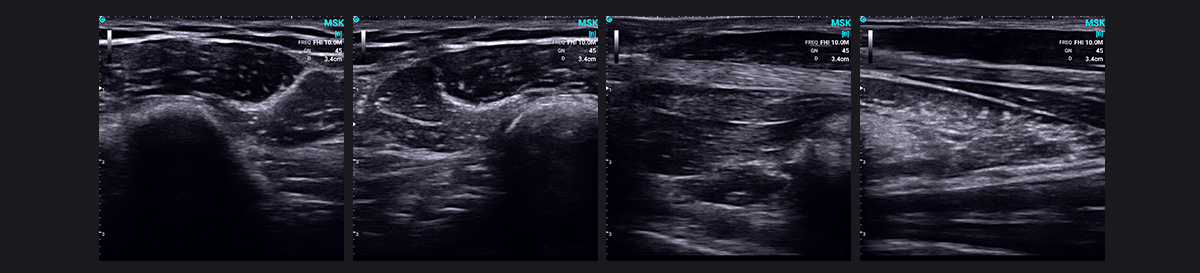

肌肉骨骼超声(MSK)近年来已成为一项突破性技术,利用高频超声来诊断肌肉骨骼系统疾病。它提供肌肉、肌腱、韧带、周围神经和其他浅表软组织结构的清晰图像,识别炎症、肿瘤、损伤和畸形等状况。

MSK 超声波在诊断关节疾病方面特别有效,包括类风湿性关节炎和痛风性关节炎。它还有助于检测代谢和全身疾病以及相关的关节。峁└髦植≈⒌娜媸油。

此外,超声波的实时动态成像功能可以检测和观察仅在运动期间或特定位置出现的异常或病变,例如肌腱和神经脱位或肩部撞击综合症。它还可以同时扫描受影响的一侧和健康的一侧,从而有助于动态比较组织结构以识别异常情况。

MSK 超声波在运动医学、创伤骨科、疼痛管理、康复和风湿病学方面有着广泛的应用。它不仅有助于临床诊断,还可以实现超声引导下的介入治疗,缩短治疗周期,改善疗效。未来,SonoEye将继续在更多医疗领域履行使命,提高患者护理和诊断精度。